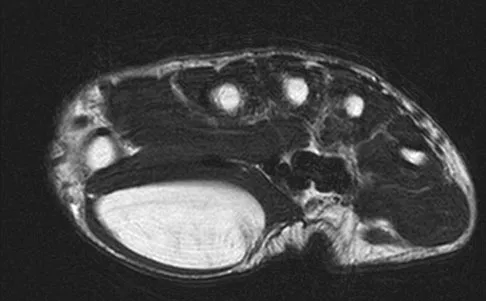

A 13-year-old girl has had right groin pain for the past 3 weeks. She denies any history of trauma. Examination of the hip reveals no palpable soft-tissue mass or lymphadenopathy, and there is full range of motion. A plain radiograph and MRI scan are shown in Figures 15a and 15b. Biopsy specimens are shown in Figures 15c and 15d. What is the most likely diagnosis?

Correct Answer: Fibrous dysplasia

Explanation:

Fibrous dysplasia frequently occurs in the proximal femur. Microfractures and remodeling can lead to the classic "Shepherd's crook deformity." The lesion has a ground-glass appearance on plain radiographs. The histologic appearance shows proliferating fibroblasts in a loose spindle cell background. Dysplastic metaplastic trabeculae are arranged in an irregular or "Chinese letter" appearance. Enneking WF, Gearen PF: Fibrous dysplasia of the femoral neck: Treatment by cortical bone grafting. J Bone Joint Surg Am 1986;68:1415-1422.